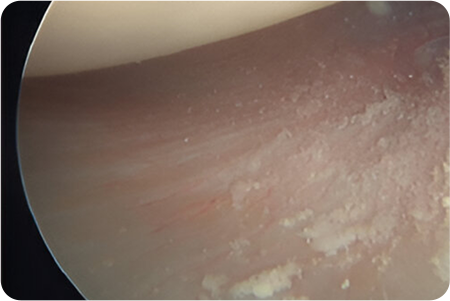

관절경하

회전근개봉합술

관절경을 어깨 관절에 삽입해 파열된 힘줄과

주변 구조를 정밀하게 확인합니다.

견봉하 공간을 넓히고 손상된 부위를 정리한 뒤,

봉합 나사를 이용해 힘줄을 원래 위치에 고정합니다.